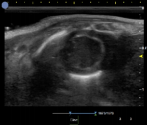

小鼠-腹主动脉彩色血流 小鼠-腹主动脉频谱多普勒 小鼠-左心室短轴 小鼠-心脏彩色血流